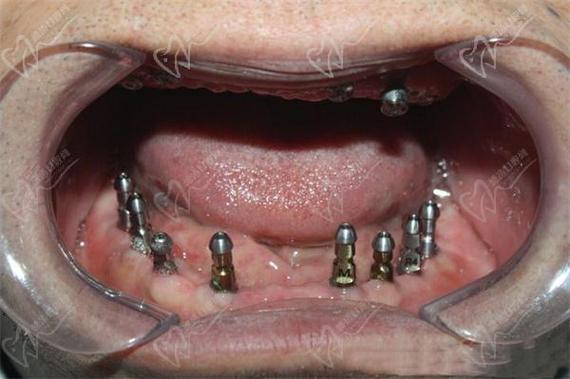

(图片来源网络,侵删)- 资质: 确认主诊医生是否有口腔种植专业相关的资质认证(如中华口腔医学会口腔种植专业委员会认证医生、ITI国际种植牙协会会员等),以及执业医师资格证。